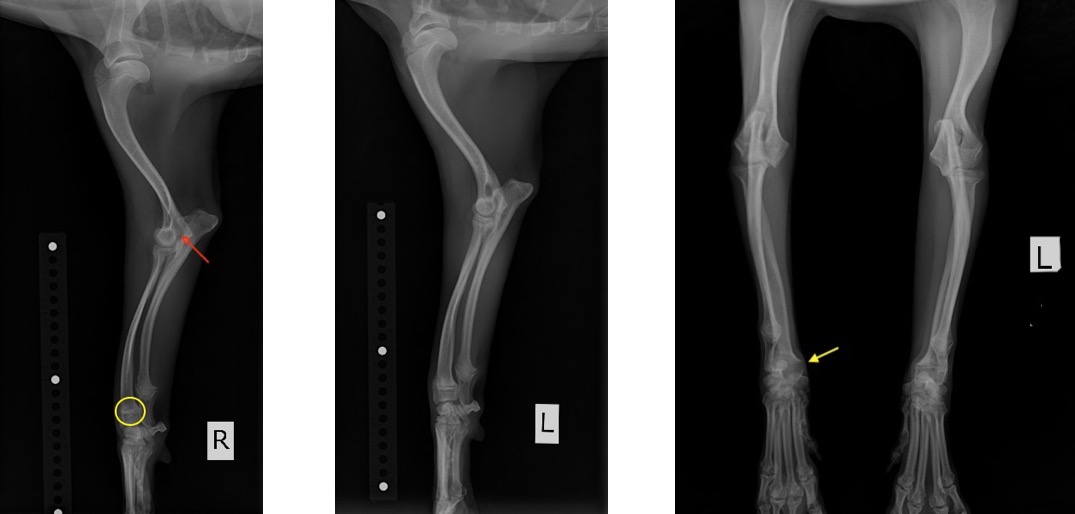

院内においても右前肢の挙上が認められ、単純X線画像検査を実施したところ、右側の橈骨遠位成長板領域の不透過性亢進、肘突起と上腕骨顆の間隙が広がっている所見が認められたため、橈骨遠位成長板早期閉鎖が疑われました。

この症例では、反対側と比較して橈骨の湾曲が顕著でなかったため、肘関節の整合性を優先し、尺骨の骨切りを実施しました。

前腕のLateral像とAP像 (黄丸と黄矢印:成長板の不透過性亢進 赤矢印:上腕骨顆と肘突起の間隙)